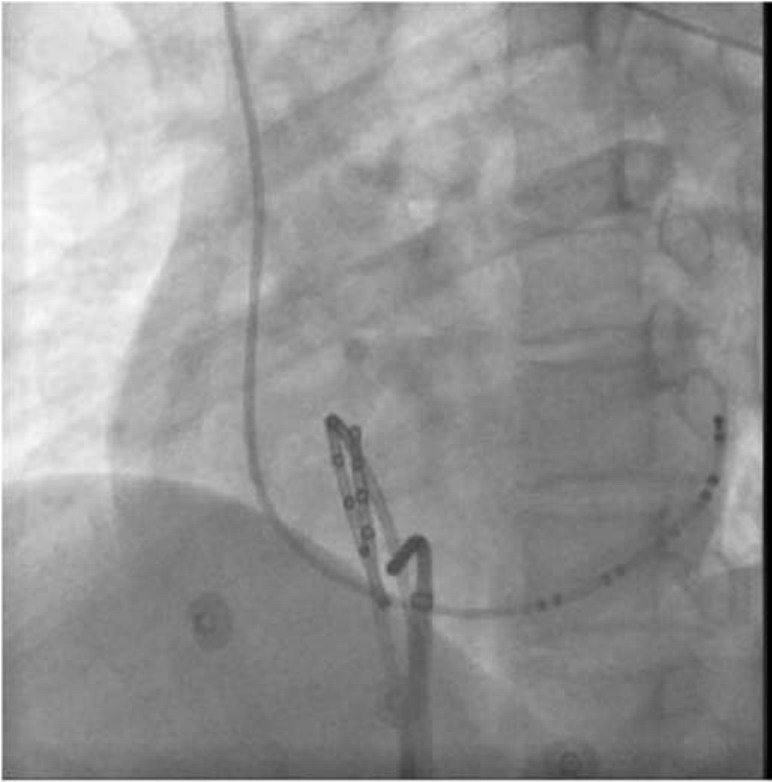

img1693

图64-11 隐匿性左侧旁路

右心室心尖部刺激S1s1=300ms,VA呈偏心性传导,逆传A波最早激动点在CS23,旁路靠近CS23。X线靶点见下图

img1694

RAO 30°

img1695

LAO 45°